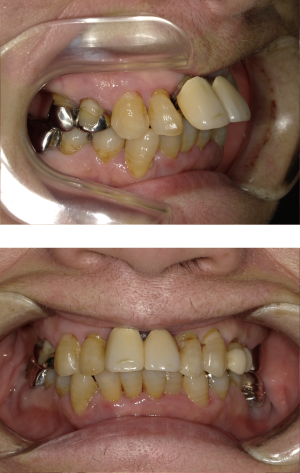

50代 インプラント治療(右上3左上3のみGBR)

| 年代・性別 | 50代・男性 |

|---|---|

| 主訴 | 入れ歯が合わず毎日ヨーグルトしか食べることができないので、しっかり咬めるインプラントにしたい。 |

| 部位 | 右下⑦⑥5④ 上顎③2①①2③ 左下67 |

| 治療期間 | 約9ヶ月 |

| 費用 | ¥4,273,500(税込) |

| 副作用・リスク |

|